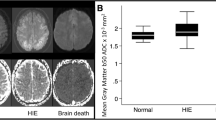

DWI showed diffuse hyperintense areas almost entirely covering both hemispheres, corresponding to diffuse edema (Fig. 2). Regional ADCav values are presented in Table 1. Additionally, in all cases, other MR images revealed diffuse sulcal effacement with hyperintense areas in both hemispheres, cerebellar tonsillar herniation, and no evidence of arterial flow in the intracranial circulation above the level of the supraclinoid portion of the internal carotid arteries (Figs. 3 and 4).

In the normal control group, the mean ADCav values were (0.76 ± 0.03) × 10−3 mm2/s for the frontal white matter, (0.88 ± 0.05) × 10−3 mm2/s for the frontal cortical gray matter, (0.72 ± 0.03) × 10−3 mm2/s for the temporal white matter, (0.86 ± 0.04) × 10−3 mm2/s for the temporal cortical gray matter, (0.77 ± 0.04) × 10−3 mm2/s for the parietal white matter, (0.87 ± 0.04) × 10−3 mm2/s for the parietal cortical gray matter, (0.72 ± 0.03) × 10−3 mm2/s for the occipital white matter, (0.85 ± 0.04) × 10−3 mm2/s for the occipital cortical gray matter, (0.69 ± 0.03) × 10−3 mm2/s for the cerebellar white matter, (0.79 ± 0.06) × 10−3 mm2/s for the cerebellar cortical gray matter, (0.75 ± 0.03) × 10−3 mm2/s for the pons, (0.76 ± 0.03) × 10−3 mm2/s for the thalamus, and (0.77 ± 0.03) × 10−3 mm2/s for the putamen. ADC values for all locations in BD patients were significantly smaller than those in control subjects (p < 0.0001; Table 2).

To our knowledge, no DWI study of BD has been previously reported. The only case report that has been published, by Lowblad and Bassetti [27], reported a decrease in the measured ADC values in the cerebral and cerebellar white and gray matter in a BD patient. We found a statistically significant decrease in ADC for all areas in patients compared with the control group. The decrease in ADC values was greater in white matter than in gray matter for both cerebral and the cerebellar hemispheres.